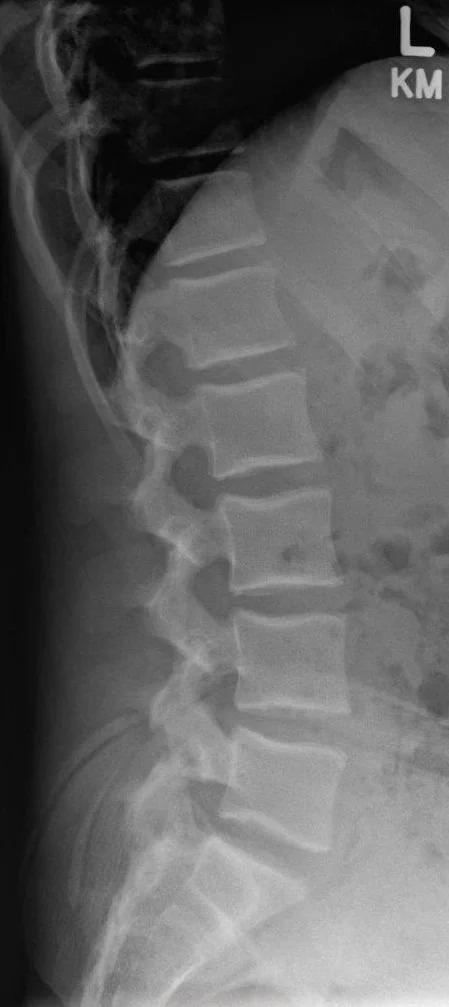

Lateral View

• Taken from the side of the patient, with the shoulder positioned closest to the X-ray detector.

• Helps visualize the disc spaces, vertebral body alignment, and the relationship between L5 and S1 from a sagittal (side) perspective.

• Images need to be taken at neutral , flexion (bending forward) and extension (bending backward) positions.